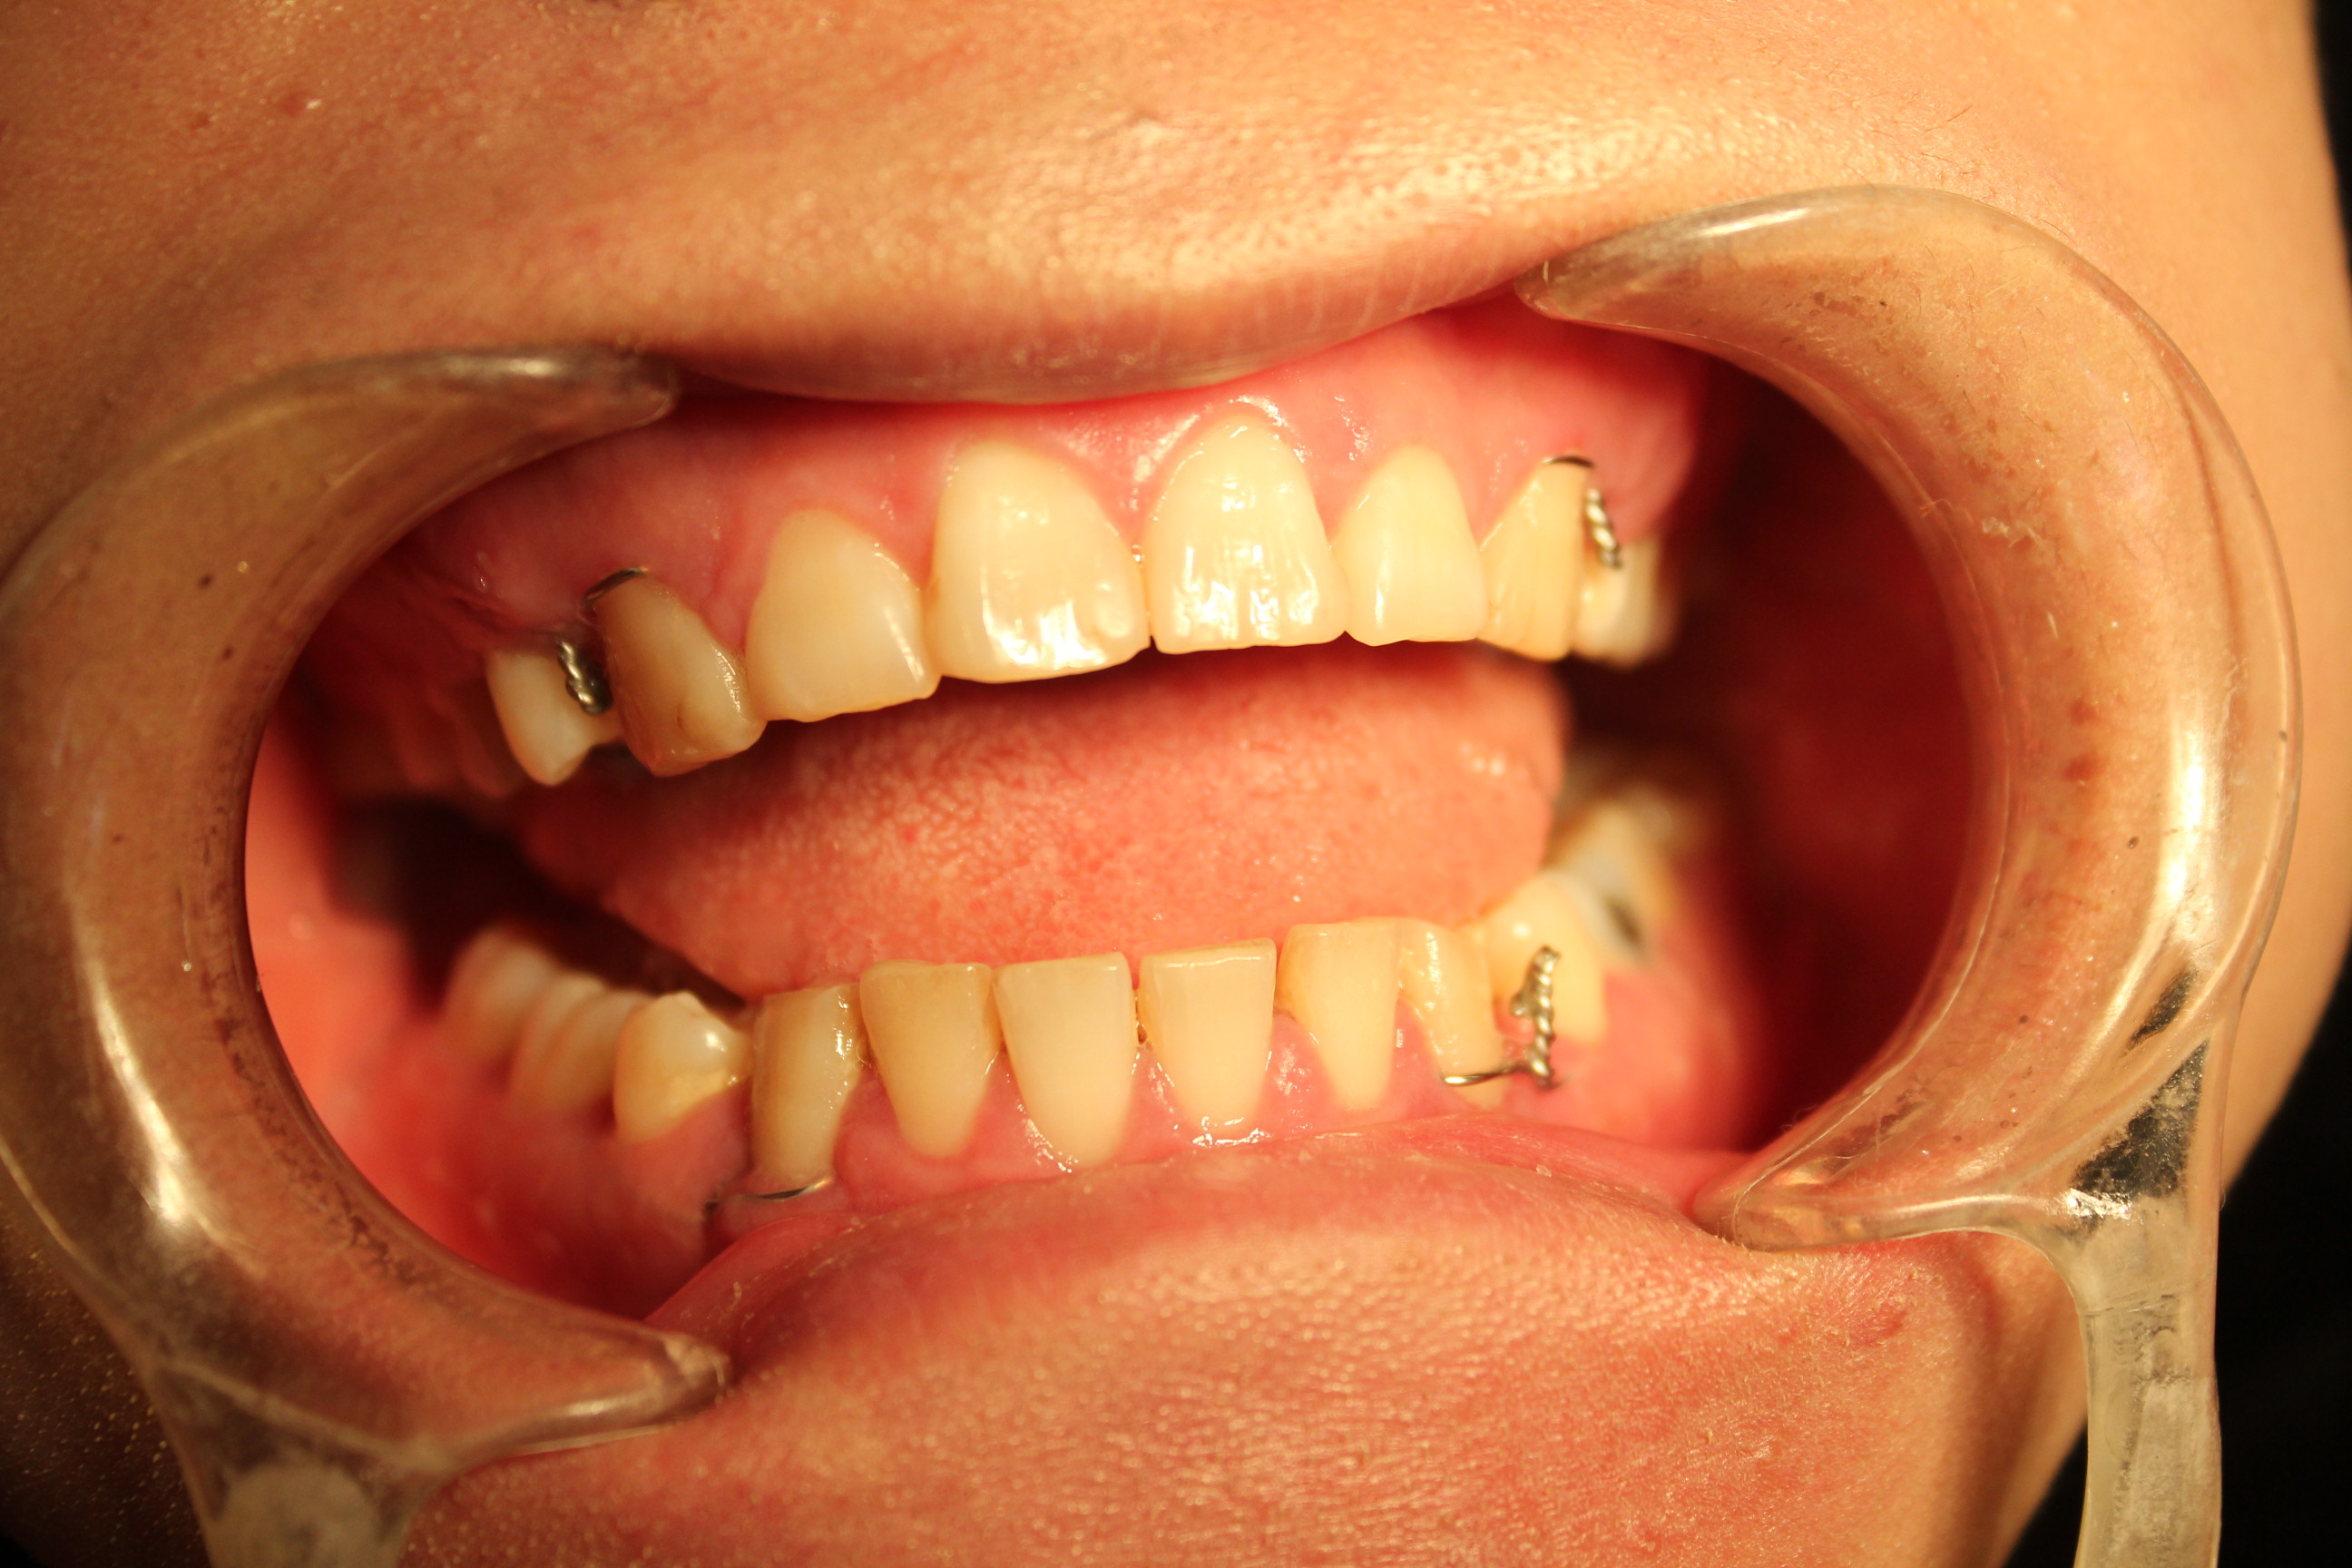

돌출입수술후 발치 치아 와이어 고정상태 - 와이어 제거전

돌출입 수술후 치아 고정 와이어 제거 후 (5개월째) - 상악치아상태